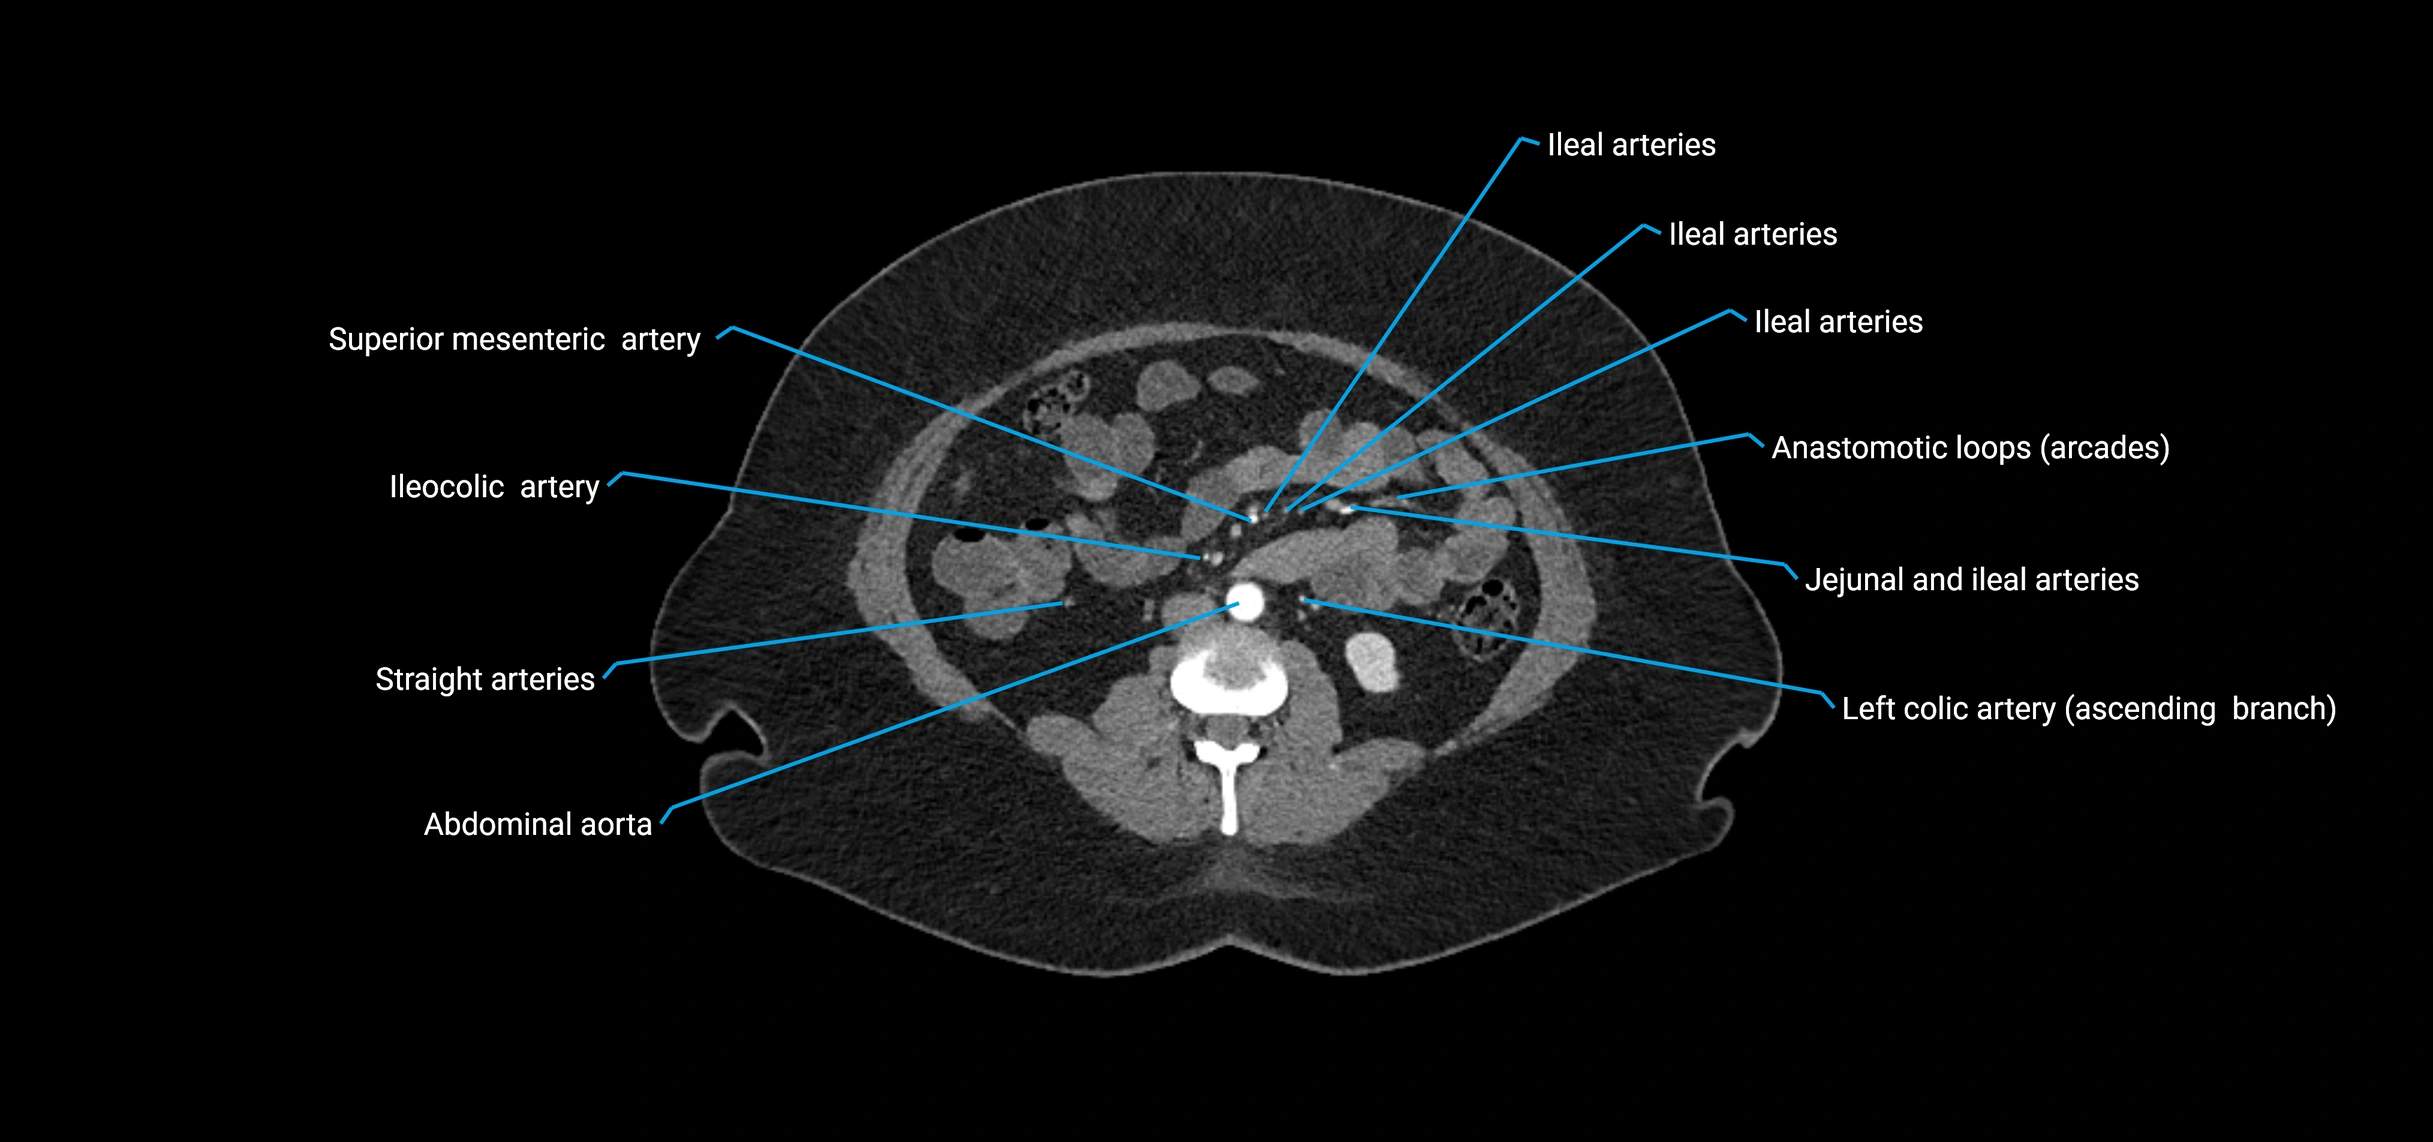

CT Appearance

Non-contrast CT:

• Appears as a tubular soft tissue structure anterior to vertebral bodies

• Calcified atherosclerotic plaques appear as hyperdense foci along the wall

• Useful for screening abdominal aortic aneurysm (AAA) size and mural calcification

Contrast-enhanced CT (CTA):

• Gold standard for abdominal aortic imaging

• Provides excellent detail of lumen, wall, aneurysm, thrombus, and branch vessels

• Multiplanar and 3D reconstructions help in aneurysm measurement, stent graft planning, and dissection evaluation

• Detects acute rupture, traumatic injury, or occlusion with high sensitivity

CT images

image